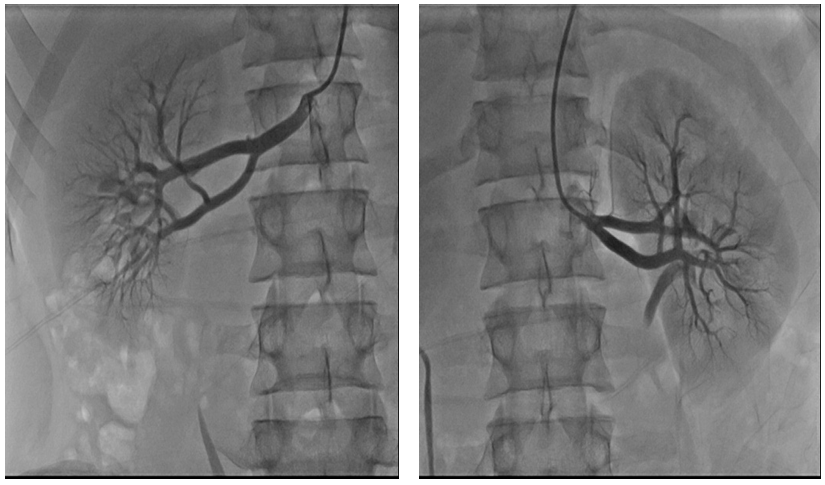

Echocardiography showed normal left ventricular dimension with moderate left ventricular hypertrophy, IVS-13mm, ZZ -11mm, and the high pressure gradient (56mmHg) by Doppler echocardiography at the across stenotic segment. This finding make a suspicion of coarctation of aorta and we done aortography (Figure 4) which confirm the diagnosis of juxtaductal coarctation. The renal angiography (Figure 5) was normal. The computed tomography (KT) aorta (Figure 6) showed juxtaductal coarctationwith high stenosis 77%-80% and prominent a.mamaria internal with collateral vessels across inferior epigastric, intercostal and scapular artery.

Figure 5: Normal renal angiography.